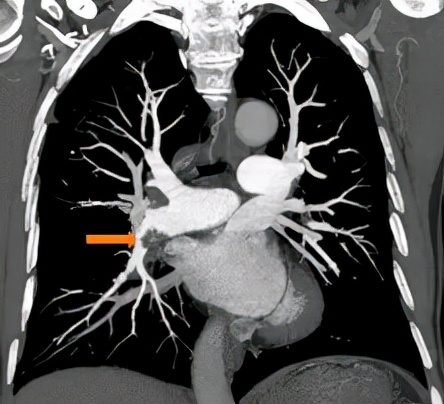

△肺动脉增强CT示:右下肺动脉主干及前基底段分支不完全性栓塞

梁伯辗转几间医院,问题都没有得到有效的解决,最终,他来到广州医科大学附属第一医院国家呼吸医学中心,入住呼吸内科病房后,医生为梁伯做了详细的检查,并通过PECT检查显示,这个阴影的代谢不强,考虑不是肿瘤, 血栓的可能性更大 。

除此之外,洪城副主任医师发现,梁伯肺部血管里面散布着 很多慢性血栓 ,考虑到他已经规范抗凝治疗三个月都还有这些血栓,初步判断为已经转化为慢性血栓,单纯的药物治疗显然已经不奏效了。

“我们发现他 双下肺、右上肺都有慢性血栓 ,如果不及时采取措施, 血栓一旦堵塞肺部的分支或主干道,形成肺栓塞,可能会引发严重后果,甚至会导致右心衰竭死亡 。”